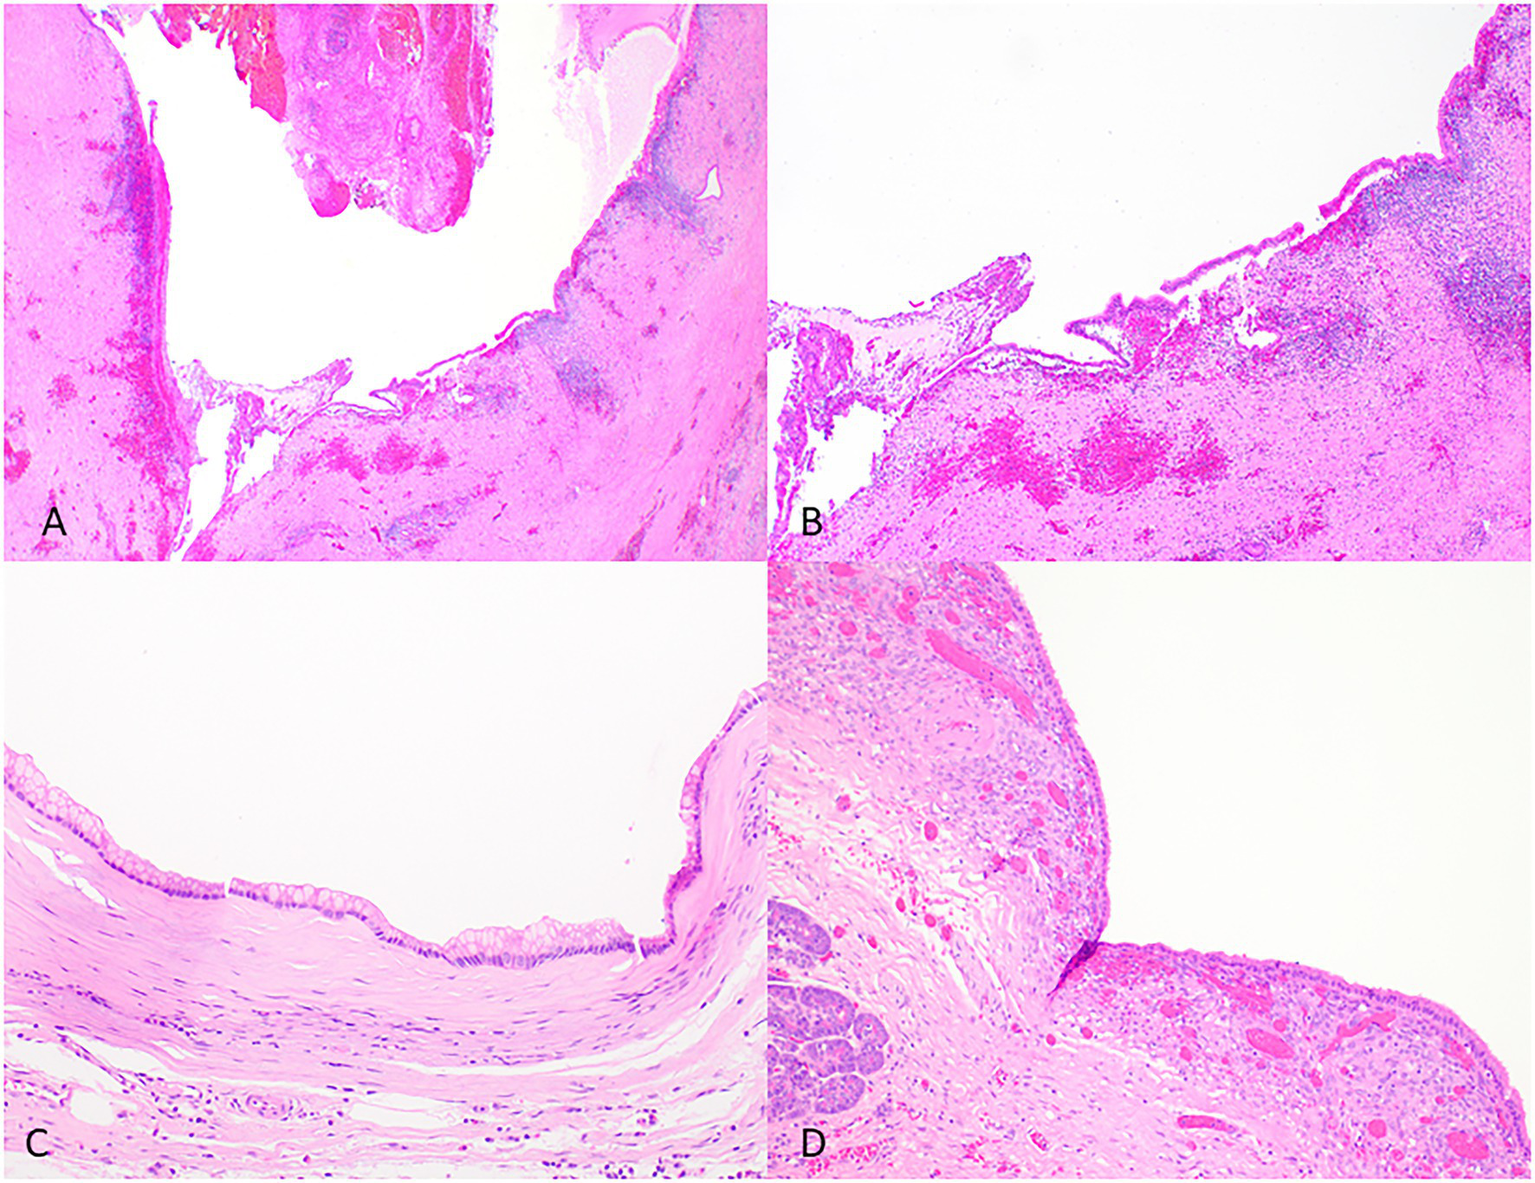

The differential diagnosis of IPMNs includes mucinous cystic neoplasms (MCNs), other intraductal neoplasms, simple mucinous cysts, and retention cysts (Figure 4 and Table 2).

Figure 4

Representative histological pictures of retention cyst, simple mucinous cyst, and mucinous cystic neoplasm. (A) Retention cyst. Low magnification shows a dilated pancreatic duct. (B) Higher magnification shows a flattened epithelium with no papillary projections. Note the background pancreas with extensive atrophy and fibrosis. No ovarian-type stroma is seen. (C) Simple mucinous cyst. The cyst is lined by a benign mucinous epithelium and lacks an ovarian stroma. (D) Mucinous cystic neoplasm. The cyst is lined by mucinous epithelium and unlike simple mucinous cyst or a retention cyst is associated with an ovarian-type stroma. (A) Original magnification 10×; (B) Original magnification 100×; and (C,D) Original magnification 200×.

Retention cysts are caused by dilatation of the pancreatic ducts due to a downstream obstructive process. They are often unilocular and lined by a flattened epithelium and lack the florid papillary projections of IPMNs (Figure 4). If no obstructive process is present, mucinous cysts larger than 1 cm and do not have characteristic histologic features of IPMN can be classified as simple mucinous cysts (Krasinskas et al., 2017). MCNs typically occur in women, almost always located in the tail or body, and do not communicate with the duct system. They contain ovarian-type stroma that can be demonstrated by immunohistochemistry staining of PR and ER (Wilentz et al., 2000; Figure 4).